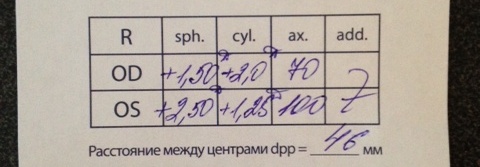

Совсем недавно заметила что левый глазик у дочки(2г6мес) немного косит. Сразу же записалась на консультацию в клинику "Ясный Взор". Проверили, оказалось, как мне объяснила врач, у ребенка большой плюс для ее возраста. Как я поняла +3.5 один глаз, второй тоже но поменьше. Выдали рецепт на изготовление очков. Сказали ходить постоянно. В январе прийти вновь на прием.

Суммарно сказала +5 на оба глаза..(

Гиперметропия ср.степени.

Астигматизм сложный гиперметропический.

Сходящееся косоглазие.

п.с кому не сложно объясните пожалуйста, что означают эти цифры?